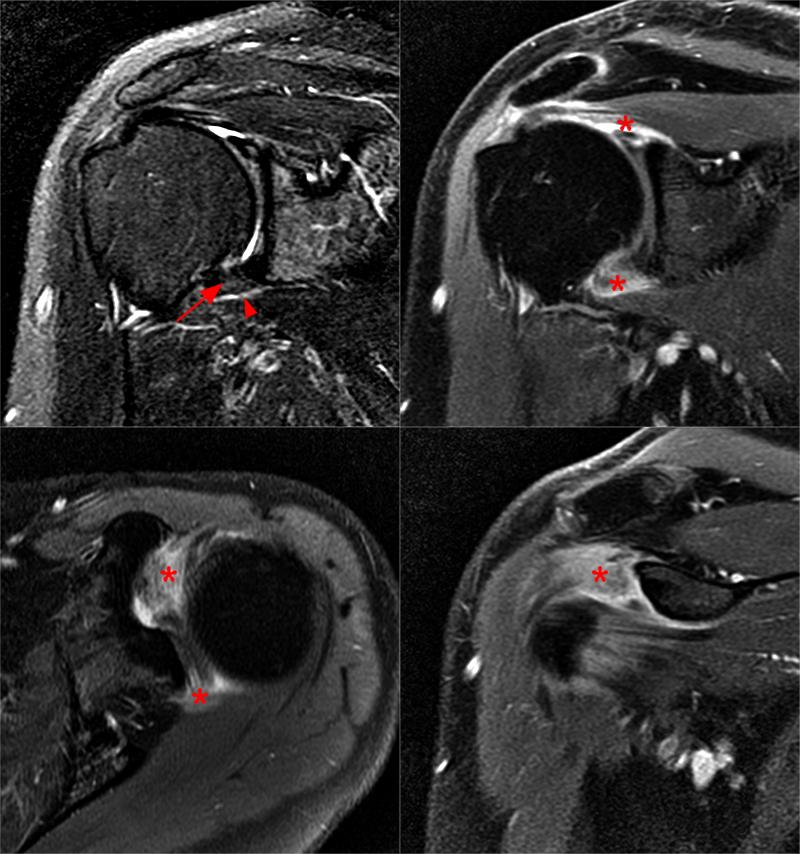

From radiopaedia.org

Adhesive capsulitis (frozen shoulder) Image Adhesive Capsulitis Stages What are the symptoms of frozen shoulder (adhesive capsulitis)? Adhesive capsulitis (also known as frozen shoulder) is a condition of the shoulder characterized by functional loss of both passive and active shoulder motion commonly associated. In this stage, your shoulder becomes. Adhesive capsulitis, also known as frozen shoulder, is an inflammatory condition characterized by shoulder stiffness, pain, and significant loss. Adhesive Capsulitis Stages.